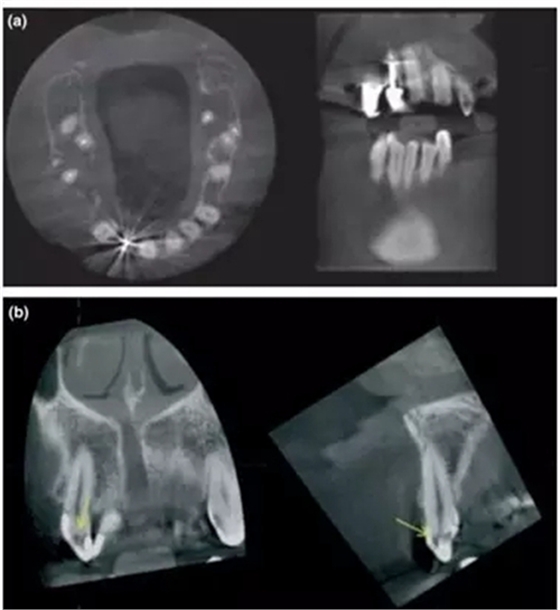

a- 右上2的金屬充填體導(dǎo)致圖像出現(xiàn)散射和射線硬化;

b- 當(dāng)散射影像與牙釉質(zhì)重疊時(shí),容易被誤診為齲齒的透射影 (黃箭頭);

另一個(gè)重要的局限性就是由高密度材料(如金屬樁和全冠)或者鄰近組織(如牙釉質(zhì))所產(chǎn)生的散射和射線硬化,對CBCT成像質(zhì)量的影響(Mora et al. 2007)。尤其當(dāng)這些影響因素特別靠近檢查區(qū)域時(shí),那CBCT就不能提供足夠的診斷價(jià)值,這時(shí)候臨床醫(yī)生就要考慮其他影像學(xué)檢查手段(Lofthag-Hansen et al. 2007; Estrela et al. 2008)。